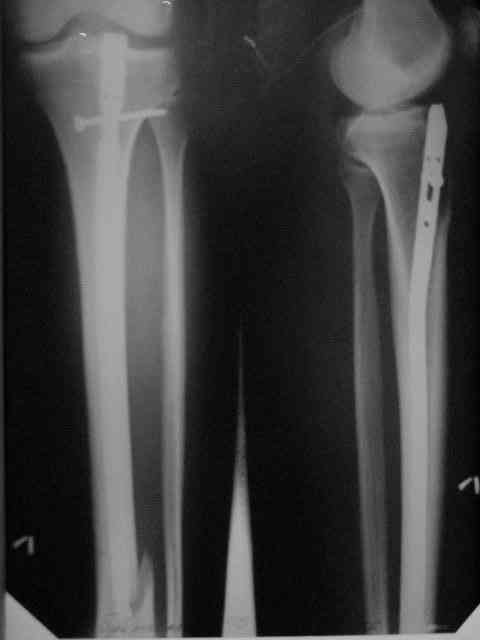

Здравствуйте коллеги!Больной 29 лет поступил 1 мая с Диагнозом: Закрытый спиральный перелом н/3 большеберцовой кости, перелом в/3 малоберцовой.

На пятые сутки выполнен вот такой остеосинтез (см R-gr) . На сегодня мы имеем перелом нижнего винта, замедленное сращение( R- gr от 11.09.06) Больного ничего не беспокоит, ходит с костылями с ограниченной нагрузкой. На наш взгляд возможно обойтись :1 Удаление сломанного винта и верхнего блокирующего с последующим более глубоким погружением штифта и его дистальным блокированием. Либо замена на более длинный (Экперт-Синтез).2 Остеотомия косая малоберцовой кости.С большим вниманием выслушаем возможные варианты, тактики в таком случае.С Уважением Владимир Бахарев.P.S Извинямси за качество снимков!

Но вопрос тут не столько в типе штифта (практически все доступные удержат дистальный отломок такой длины, и более дорогой стержень не даст тут выигрыша, адекватного разнице в цене), а в том, как должны располагаться отломки и штифт. Вот с этим в застарелом случае при околосуставном повреждении обычны трудности.

Большого ротационного смещения вроде не видно. IMHO здесь надо бы 1)восстановить длину (дистрактор) - возможно, получится одномоментно.

2)Устранить смешение периферического отломка кнаружи - спереди назад отклоняющие (poller) спицы или винт ввести, чтобы оттеснить штифт к латеральной стенке. Понятное дело, ввести гвоздь дистальнее, чем этот сейчас. Запереть можно сразу динамически.